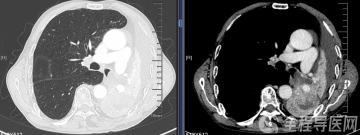

轻度氟斑牙患者诊室漂白前后对比

氟斑牙患者诊室漂白联合渗透树脂前后对比

氟斑牙患者贴面修复前后对比